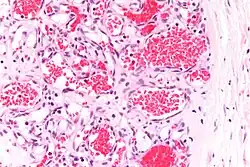

![]() |

Capillary hemangioma | Micrograph showing capillary hemangioma of skin. | Category: Histopathology of capillary hemangioma | Capillary hemangioma |